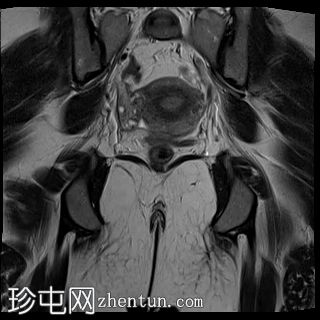

冠状位

T2加权像

MRI特征符合剖宫产术后瘢痕子宫内膜异位症,表现为特征性T1高信号伴T1FS持续存在,T2低信号伴内部高信号灶,病灶边缘浸润于腹前壁肌肉内,以及对比增强。

该病灶累及腹白线并浸润腹直肌,主要位于中线左侧,耻骨联合及结节处腹直肌起点上方。

影像学表现符合病灶内出血成分,提示既往剖宫产瘢痕处存在异位子宫内膜组织。

子宫可见剖宫产瘢痕灶。